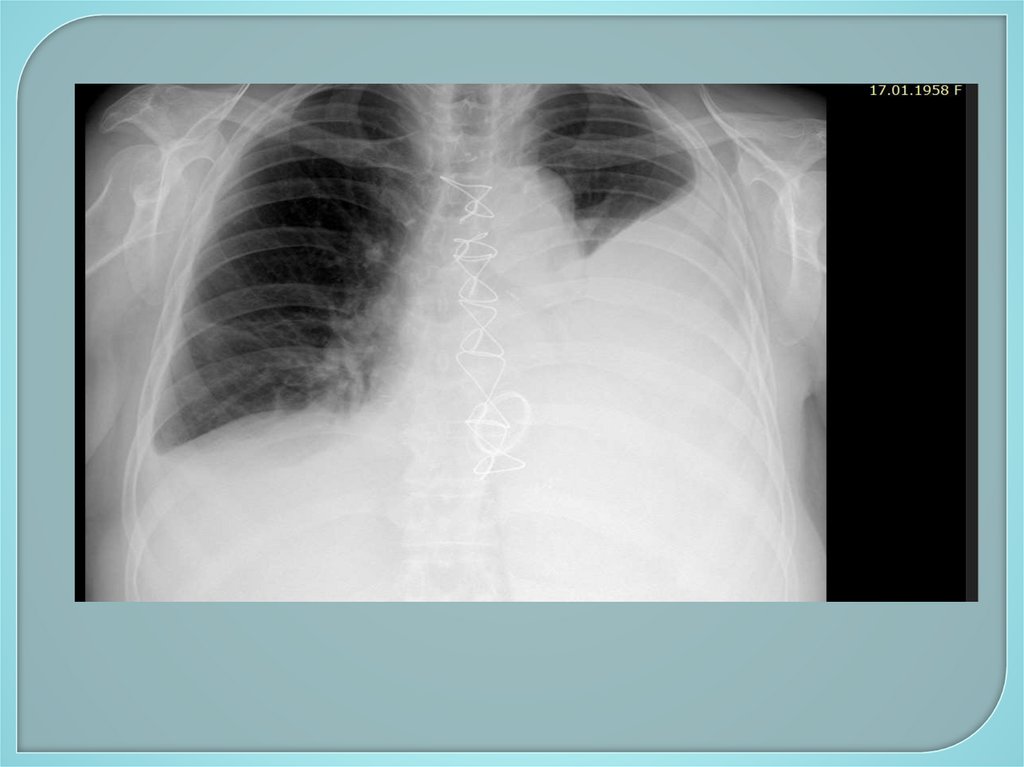

Двусторонний гидроторакс. Состояние

после протезирования митрального клапана